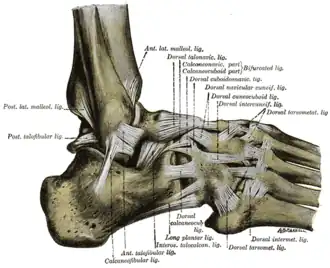

- Pijn bij palpatie van de distale 6 cm van de posterieure zijde van het scheenbeen of de knobbel van de binnenenkel;

- Pijn bij palpatie van de distale 6 cm van de posterieure zijde van het kuitbeen of het uiteinde van de buitenste enkelknobbel;

- Pijn bij palpatie van de basis van het voetwortelbeentje van de kleine teen;

- Pijn bij palpatie van het os naviculare.

- Gevoeligheid ter hoogte van de 6 cm lange Posterieure rand van de laterale Malleolus

- Gevoeligheid ter hoogte van de 6 cm lange Posterieure rand van de mediale Malleolus